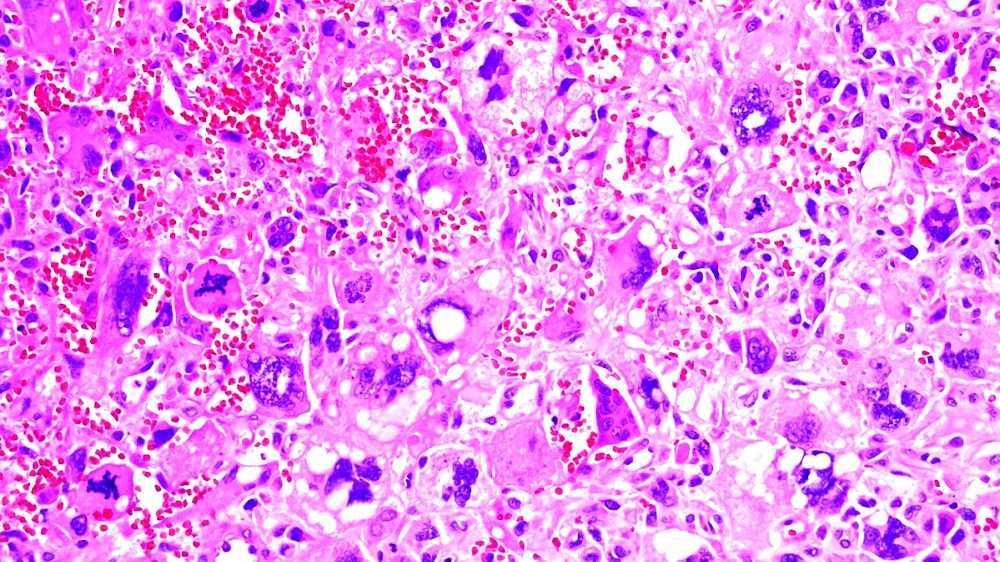

The image is showing spindle cell carcinoma, small islands and, cords... Download Scientific Spindle Cell Lung Cancer Spindle cell carcinoma is an aggressive (rapidly developing) malignancy that has elements of both carcinoma and sarcoma. There are only 13 reported cases in literature, only three of which had a survival of more than 11 months. Here we present a case of spindle cell carcinoma that proved difficult to diagnose in the absence of surgical lobectomy. Due to the. Spindle Cell Lung Cancer.

Giantcell carcinoma of the lung Spindle Cell Lung Cancer Spindle cell carcinoma is an aggressive (rapidly developing) malignancy that has elements of both carcinoma and sarcoma. There are only 13 reported cases in literature, only three of which had a survival of more than 11 months. Therefore, the prognosis and treatment of pulmonary scc is unclear. Spindle cell carcinoma (spcc) is defined as a rare histological type of sc,.. Spindle Cell Lung Cancer.